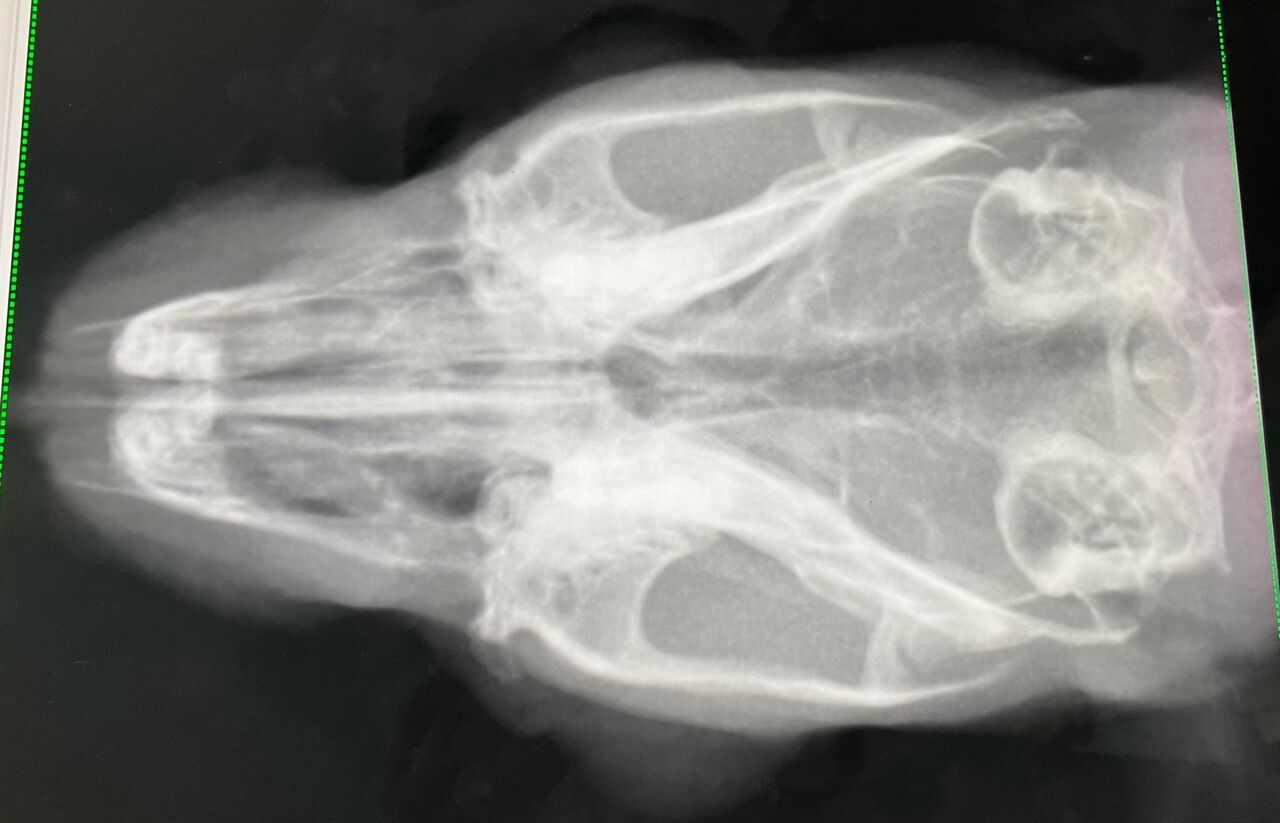

【血液検査とレントゲン】

※クリックで拡大見れます